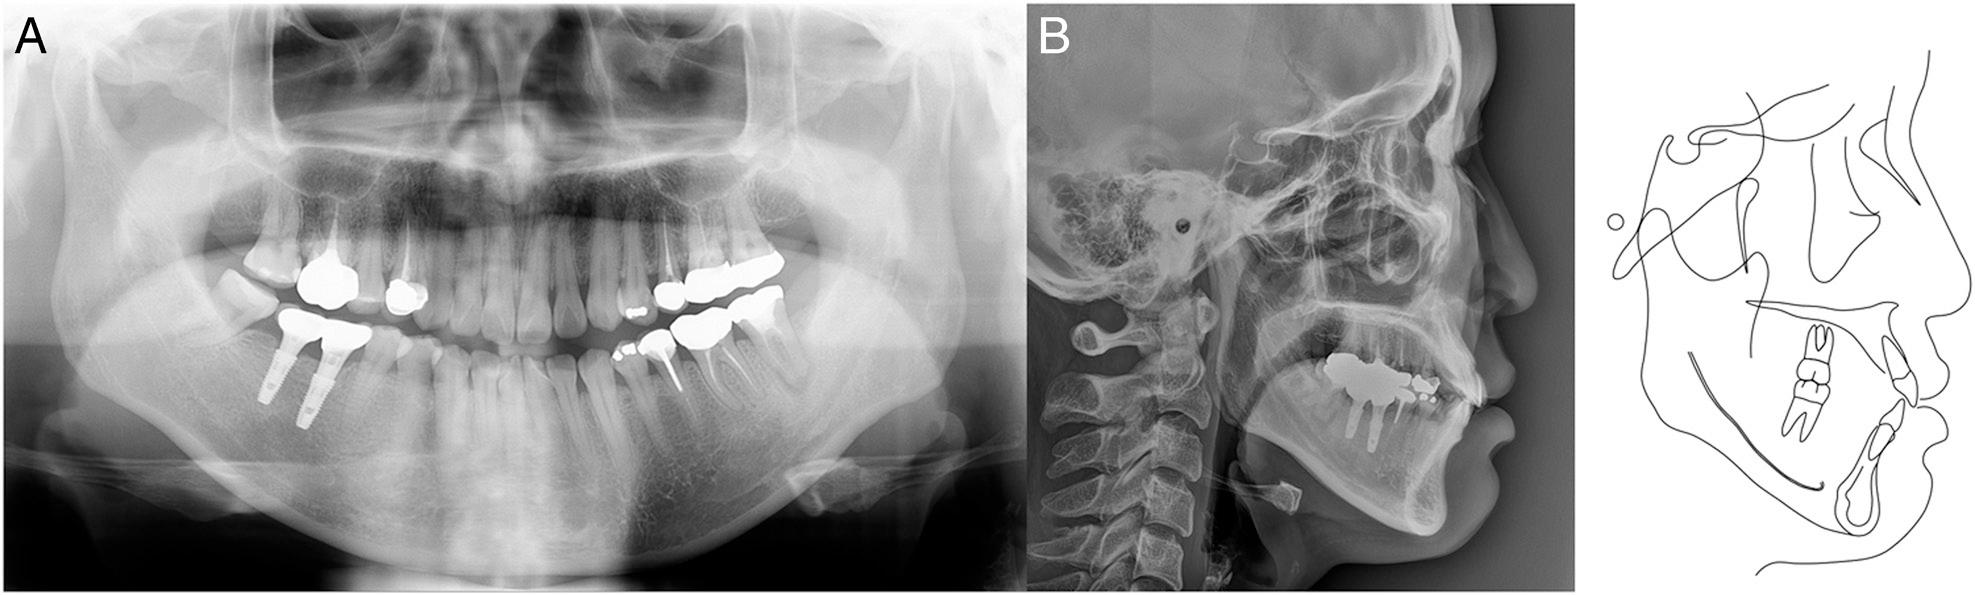

Figure 1.

Figure 2.